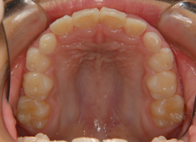

上顎前突(出っ歯)10歳男子

治療前

出っ歯治療後

①主訴:出っ歯を治したい

②診断名あるいは主な症状:上顎前歯の前方への突出

③年齢:10歳

④治療に用いた主な装置:ライトワイヤー +(機能的矯正装置)

⑤抜歯部位:非抜歯

⑥治療期間:約1年半~2年

⑦治療費:検査:38,500円

基本矯正費用:440,000円~

調整料:6,600円 (ひと月に1回)

⑧リスクと副作用:治療開始後数日は噛むときに痛みがあります。

虫歯予防のため適切な歯磨きが必要

装置が破損することがあるため、その時は連絡をすること

後戻り防止のため、保定装置の装着が必要である。

第2期(永久歯列期)での仕上げの治療が必要になる場合もある